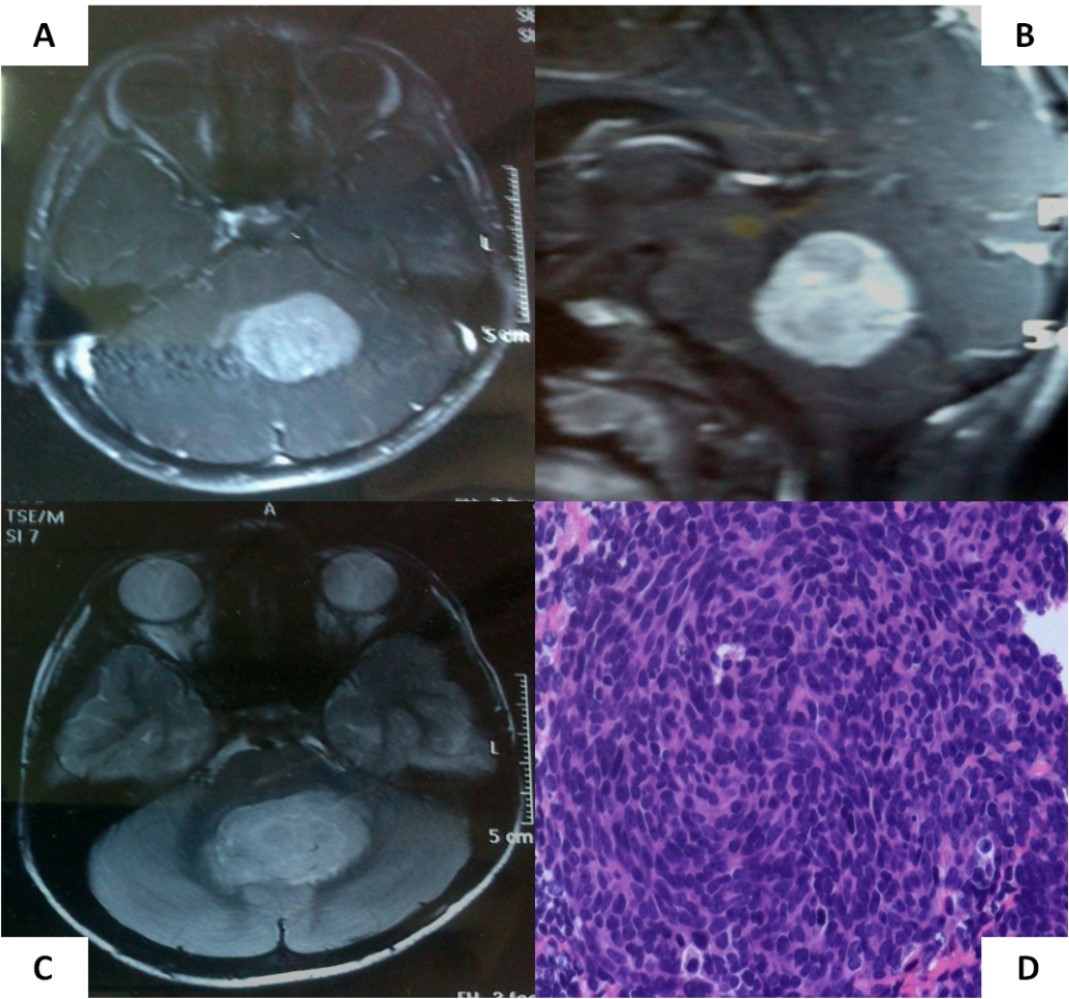

A 6-year old boy initially presented to us with headache, vomiting, and ataxia of 6-months duration. Cranial magnetic resonance imaging (MRI) showed a large lobulated, midline vermian space-occupying lesion, hypo-to iso-intense on T1-weighted images, hyperintense on T2-weighted and FLAIR images with prominent and homogenous enhancement post-contrast (Figure 1A-C) with aqueductal compression causing supratentorial hydrocephalus suggestive of medulloblastoma. He underwent near-total excision of the vermian space occupying lesion at an outside hospital that was reported as classical medulloblastoma on conventional light microscopy (Figure 1D). The non-availability of formalin-fixed paraffin embedded tumor tissue blocks precluded further molecular subgrouping of medulloblastoma. Post-operative MRI revealed the presence of two small residual enhancing nodules at the edge of the resection cavity. Neuraxial staging using MRI of the spine with gadolinium and cerebrospinal fluid (CSF) malignant cell cytology via a lumbar puncture did not show any evidence of leptomeningeal dissemination. Although there was no evidence of leptomeningeal metastases (M0 status), he was categorized as high-risk disease by virtue of residual tumor volume >1.5 X 1.5cm2 as per the prevalent risk-stratification system, and treated on an ongoing institutional phase II study of concurrent carboplatin with standard-dose craniospinal irradiation with posterior fossa boost followed by six cycle of multi-agent adjuvant systemic chemotherapy. Neuraxial imaging after completion of adjuvant therapy showed complete resolution of residual enhancing nodules with reactive gliosis.

Figure 1.Pre-operative MRI of the brain showing a brilliantly enhancing midline vermian lesion in axial (A) and sagittal (B) T1-weighted post-contrast images with variable intensity on T2-weighted images (C). Photomicrograph of the tumor (D) showing it highly cellular tumor composed of small blue round cells consistent with classic medulloblastoma (X 400, hematoxylin & eosin)